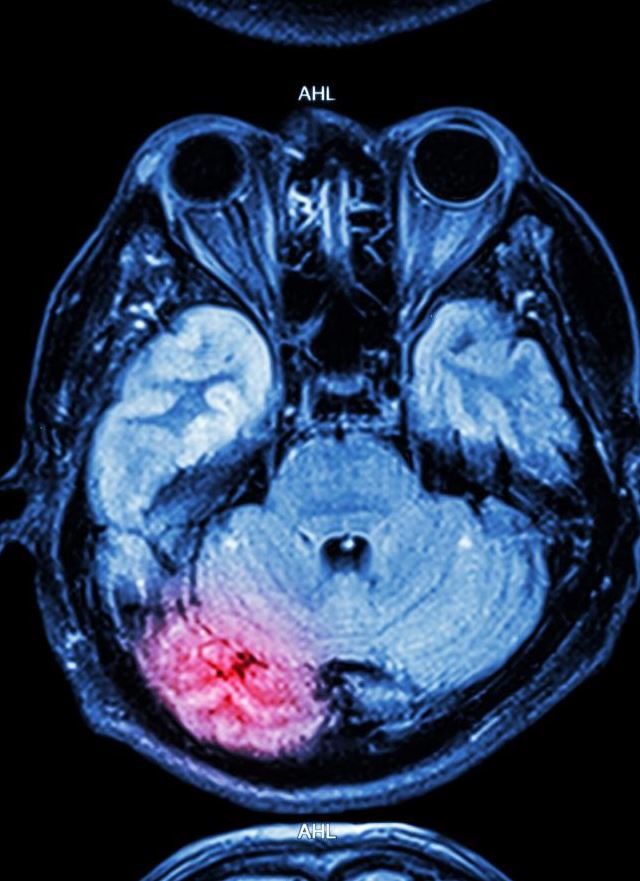

L’ictus si verifica quando il flusso sanguigno diretto a una parte del cervello viene interrotto: a causa dell’ostruzione di un’arteria (ictus ischemico) oppure per la rottura di un vaso (ictus emorragico). In Italia, ricorda Il Messaggero, si registrano tra 120.000 e 150.000 casi ogni anno, una cifra enorme che conferma quanto questa malattia sia purtroppo ancora una delle principali cause di morte e disabilità.

Chi sopravvive può trovarsi ad affrontare afasia, difficoltà motorie, perdita di autonomia e di ruolo nella vita quotidiana. Un quadro che peggiora minuto dopo minuto, se il trattamento non arriva tempestivamente.